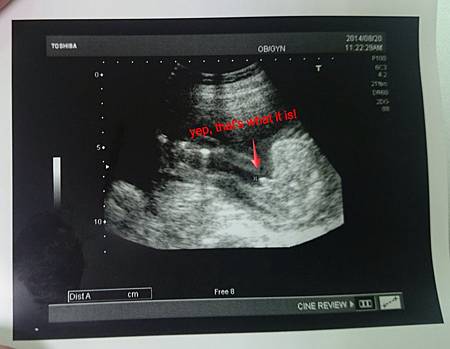

於是,就在20週第二次產檢時,答案終於揭曉了!

超音波師先看了一下頭圍和大腿骨的長度(很好,都有符合預估的週數),然後拍了拍他的兩隻手手還有腳底板,接著,就在我還沒回神,超音波師冷不防地從臀部往上一照:

是∼阿∼柴∼!就這樣,這小子居然讓我和宅老公以為他是個妹妹,誤會了這麼久!我看,他出生之後,勢必會調皮到讓我傷腦筋吧!